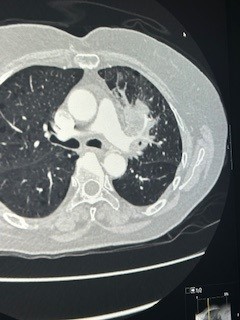

Στις φωτογραφίες 1 και 2 φαίνεται μεγάλος όγκος αριστερού πνεύμονος που εμφάνισε απόστημα και σηψαιμία. Οι λεμφαδένες που κατεγράφησαν στην αξονική και στο PetScan χαρακτηρίστηκαν καρκινικοί λεμφαδένες και το περιστατικό είχε χαρακτηριστεί ανεγχείρητο. Μια γενναία απόφαση της ομάδας μας, οδήγησε τον ασθενή σε αριστερή πνευμονεκτομή, όλοι οι λεμφαδένες ήταν αρνητικοί για κακοήθεια (ήταν έντονα φλεγμονώδεις και έδιναν ψευδή εικόνα) και κανένα από τα υπόλοιπα όργανα δεν είχαν διηθηθεί παρά τη γειτνίαση με τον όγκο (αορτή, μεσοθωράκιο, τραχεία). Η ασθενής είναι σε άριστη κατάσταση και είναι σε πρώτο κύκλο χημειοθεραπείας.

Photo 1

Photo 2